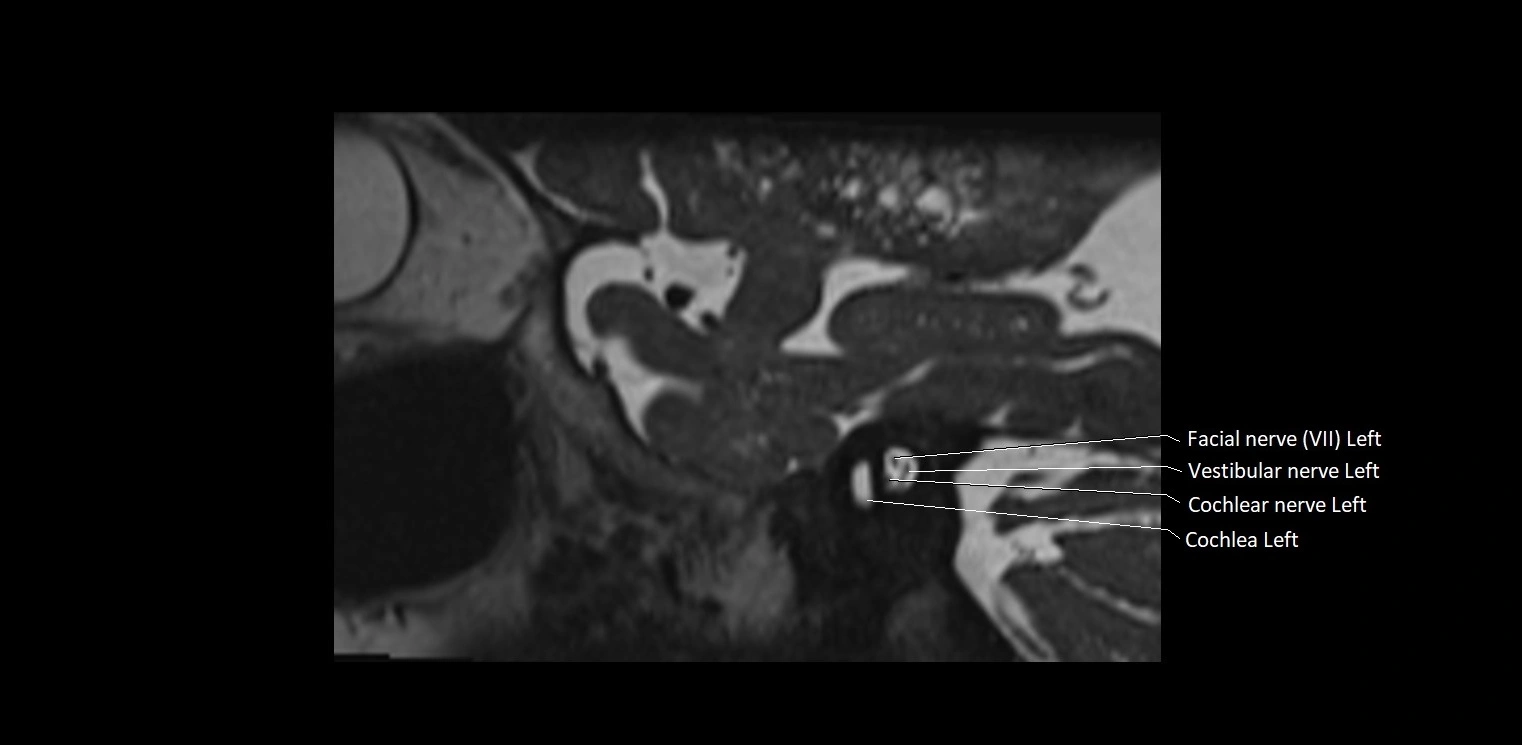

MRI images

image